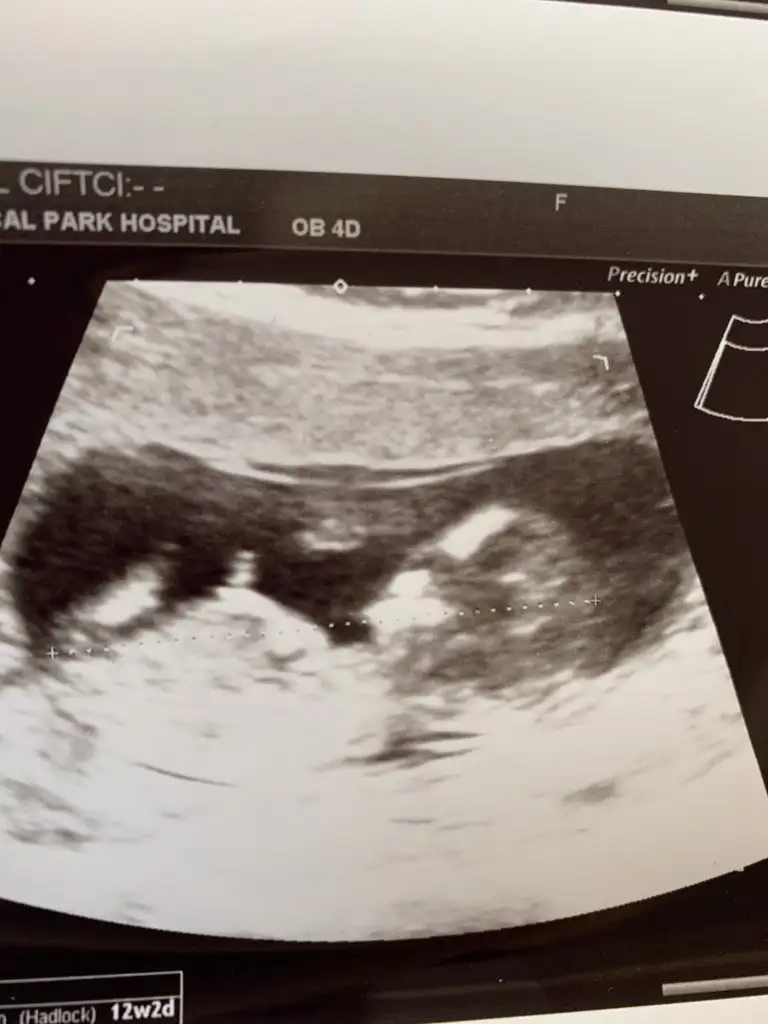

dr soylemeden siz gorun genital nub teorisi ( bebegin cinsiyeti)

Banada tahminde bulunabilir misinizzz🥰

Eklentiler

• 3885AD85-6BBA-4800-82D2-A71289D3C3C0.webp

3885AD85-6BBA-4800-82D2-A71289D3C3C0.webp

22,7 KB · Görüntüleme: 57